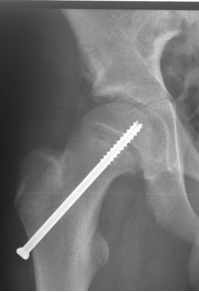

Teleskopnagelung in der Osteogenesis imperfecta-Behandlung

Bei der operativen Behandlung steht die Versorgung von Knochenbrüchen oder Achsfehlstellungen mit Teleskopnagelungen im Vordergrund. Aus orthopädischer Sicht ist trotz ständiger Bruchgefahr viel Bewegung wichtig, um eine stützende Muskulatur aufzubauen und Skelettveränderungen vorzubeugen bzw. zu verzögern.